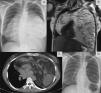

Una mujer de raza blanca, de 39 años de edad y ex-fumadora (índice de consumo de cigarrillos: 6), fue derivada a la consulta ambulatoria por una anomalía detectada en una radiografía de tórax, en la que se observaba una opacidad de gran tamaño con el signo de la silueta cardíaca (fig. 1). Se practicó una tomografía computarizada (TC) torácica, que mostró una masa que ocupaba gran parte de la cavidad torácica. Los resultados de la evaluación histopatológica de la lesión sugirieron un diagnóstico de timoma. La resonancia magnética (RM) no indicó invasión de las estructuras circundantes. La paciente se sometió a una toracotomía bilateral, extirpándose un timolipoma de 3,9kg. Como puede observarse en la imagen, la radiografía de tórax efectuada después de la intervención quirúrgica mostró la expansión completa de ambos pulmones.

A) Radiografía de tórax (proyección posteroanterior) en la que se observa una opacidad de gran tamaño, y el signo de la silueta cardíaca. B y C) RM y TC torácicas que muestran una masa muy heterogénea, que rodea al corazón por ambos lados. D) Radiografía de tórax (proyección posteroanterior) efectuada después de la resección quirúrgica, en la que se observa la expansión de ambos pulmones.